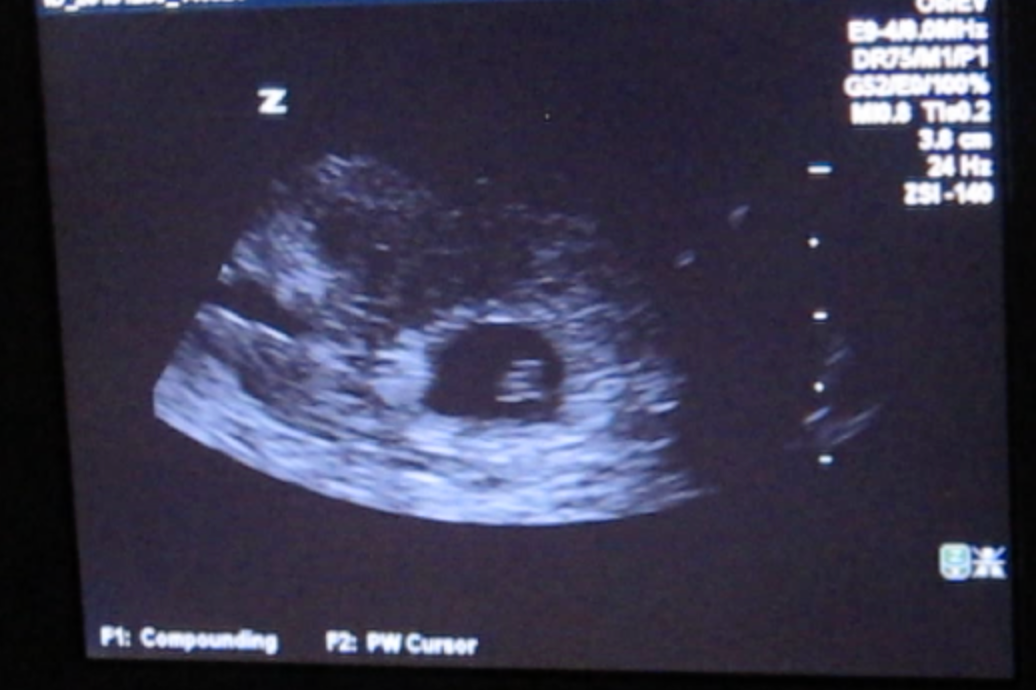

Our first appointment was exciting. Without a hitch. We even got to hear the baby’s heartbeat! We thought nothing of it when the OB-GYN asked me to remind her when the first day of my last period was, and if there was any chance it had been late. Nothing to worry about, she said – sometimes they track a little small but most of the time they catch up, and due dates can always be a little off.

The technician spent a long time with us. She kept moving the probe around for what seemed like a full half hour, as if she was looking as hard as I was praying. When we asked, she said she isn’t allowed to interpret what she sees, that she can only share the report with the physician who then interprets for us. We were wheeled back to our little room in the emergency department and waited and waited. When the on-call OB came in, she confirmed the worst, with a tone of voice indicating that despite having had to deliver the message time and time again, it never got easier: “We couldn’t find a heartbeat. I’m sorry.”